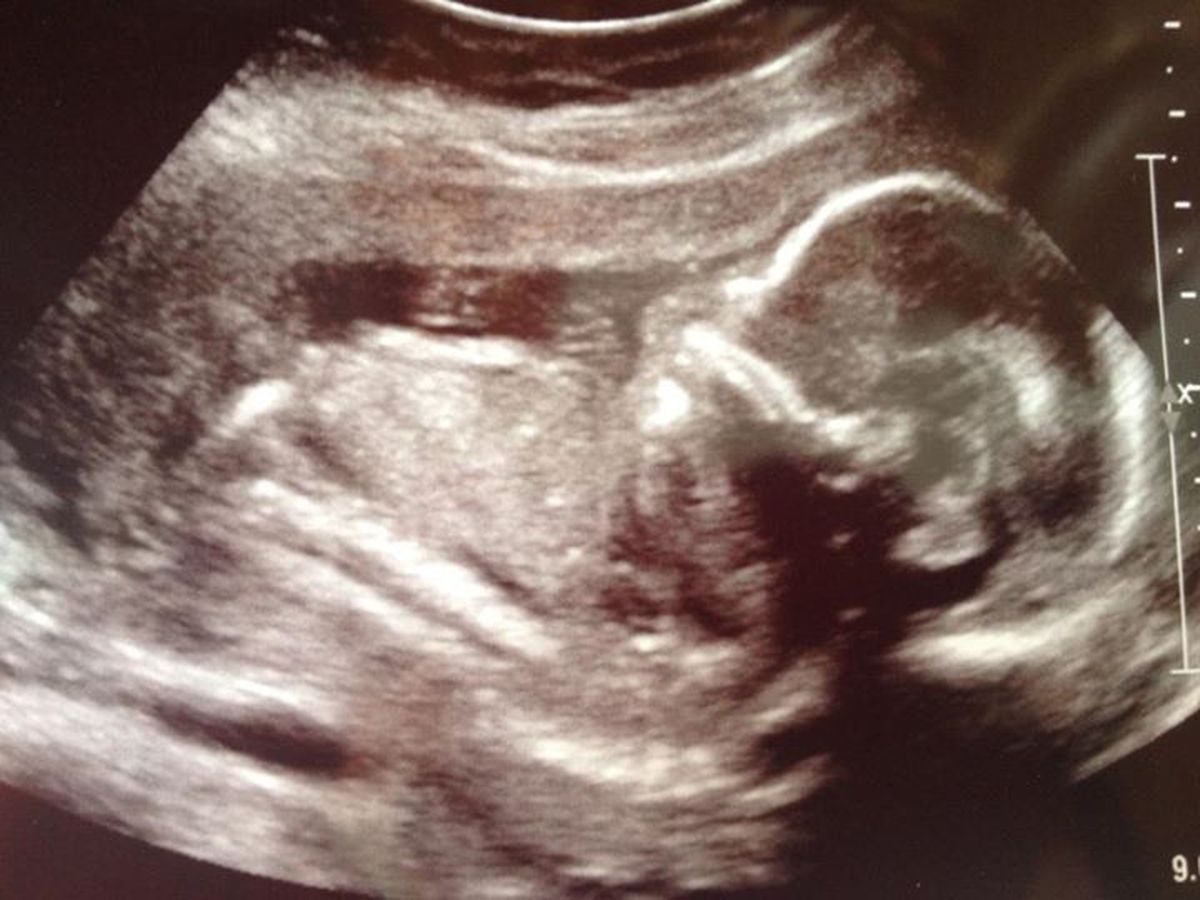

The Love family is also expecting a baby boy. He is scheduled to be delivered in Boston on January 20th, 2014. His prognosis has been very poor. Mommy traveled to Albany and Boston for amnio-infusions to increase the hope that he may survive. Recently the family received the most heartbreaking news... Baby boys chest cavity is extremely small in size and his heart is taking up all of the space. This indicates he may very well be incompatible with life. The family is still remaining on to the hope that the last few weeks created a miracle.